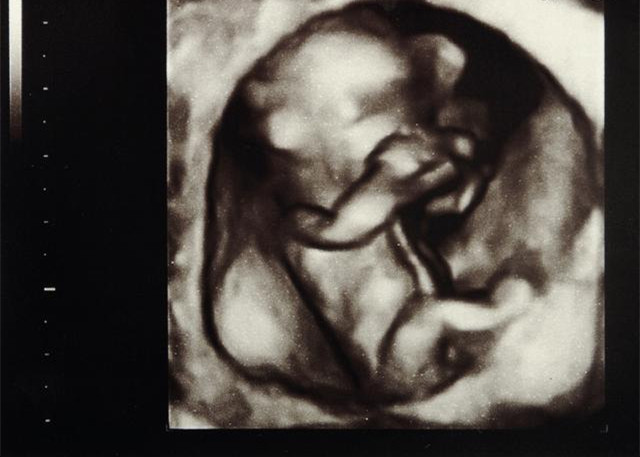

1、胚芽正在子宫深处迅速生长,这时候胚胎宝宝长度约0.4~0.5厘米,有一个小苹果籽大小,但是看起来还不像人,更像一只小蝌蚪。2、本周胎儿的心脏开始有规律的跳动及供血。细胞迅速分裂,主要的器官如肾脏和肝赃开始生长。连接脑和脊髓的神经管也开始工作,原肠开始发育。

3、胚胎的上面和下面开始形成肢体的幼芽,将来形成宝宝的手和腿。

4、面部器官本周开始形成,鼻孔可清楚地看到,眼睛的视网膜也逐步成型。

5、将来形成嘴巴的地方的下方有些小的皱摺,它以后会发育成宝宝的脖子和下巴。

结语:怀孕是个漫长的过程,刚开始大家都难以置信,肚子里原来有个小东西,在两个月的时候,胎儿已经以然成形,用眼睛是看不到的,孕妈妈只能用内心去感受,用B超去观察。